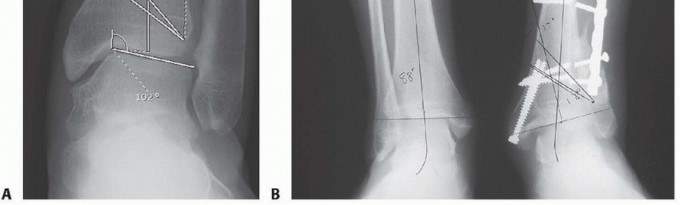

## For varus deformities, an opening wedge is created along the same line. Once the osteotomy is made, the osteotomy site is distracted using a lamina spreader to the preplanned distance to correct the deformity (TECH FIG 4A-C).

## It is then held open by a wedge-shaped tricortical iliac crest graft or simply stabilized with a medial plate and screws (TECH FIG 4D-H), beginning with a screw passed from medial to lateral across the osteotomy site.

TECH FIG 4 • A. Position of the two Crego elevators used to protect the soft tissues during the oblique osteotomy. An oscillating saw is used to create the oblique osteotomy. Fluoroscopy is used to confirm the angulation of the cut as well as to ensure that the lateral cortex remains intact. B. A large osteotome is placed into the osteotomy site and used to open the osteotomy. C. A laminar spreader is used to hold open the osteotomy site. D. The amount of medial opening needed for deformity correction is verified by measuring the medial opening in millimeters. (continued)

P.563

## TECH FIG 4 • (continued) E. A bicortical 3.5-mm screw (cortical) is inserted from the proximal to distal fragments to hold the osteotomy site open, allowing for removal of the laminar spreader. F. A 3.5-mm small fragment dynamic compression plate is contoured to the medial aspect of the distal tibia. G. The plate is secured to the distal tibia with 3.5-mm cortical bone screws. H. Intraoperative AP radiograph showing opening wedge osteotomy with internal fixation.